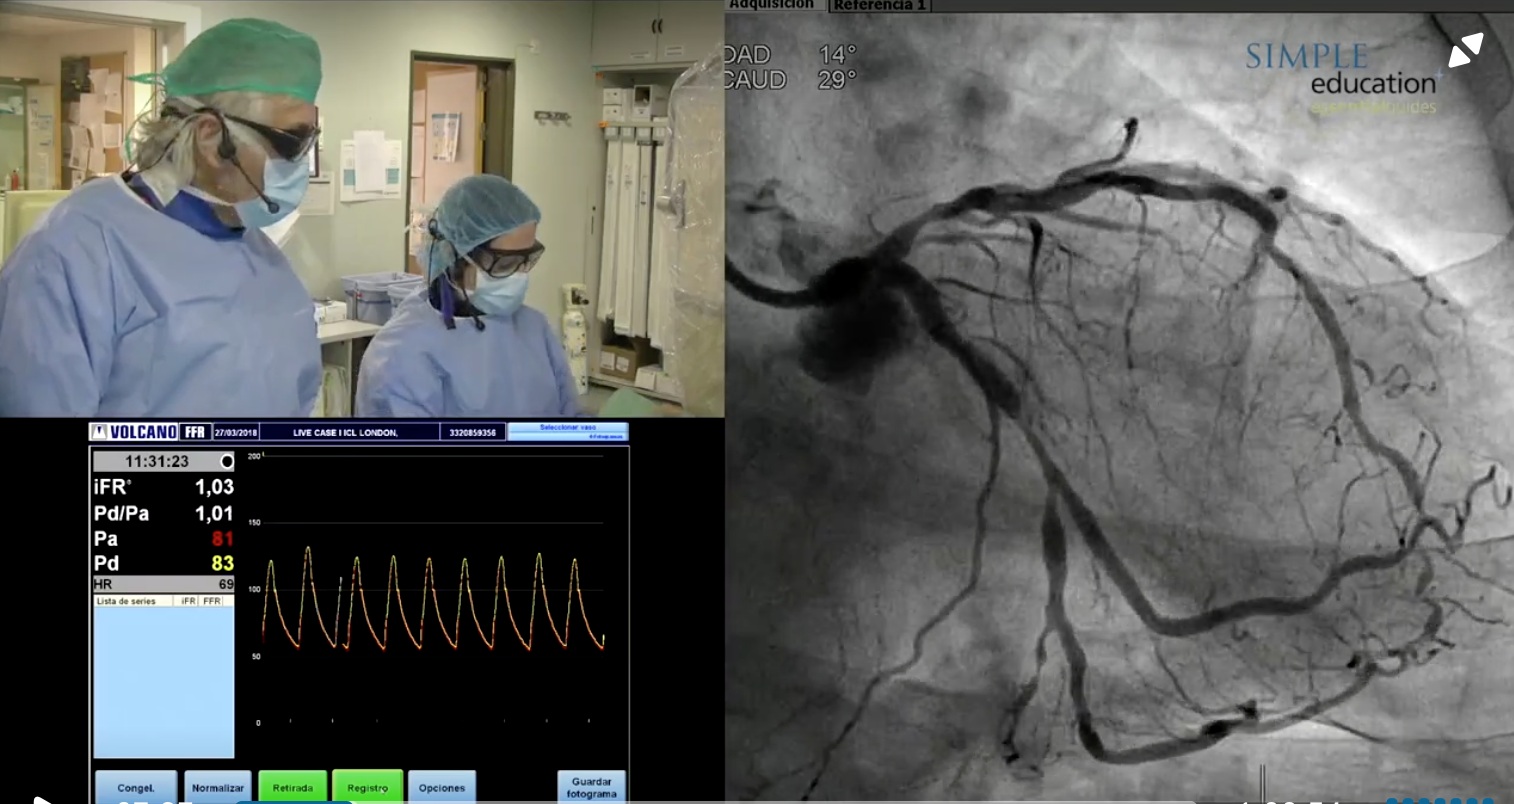

Prof Javier Escaned and Dr Nieves Gonzalo provide a live case transmission from Clinico San Carlos, Madrid, Spain.